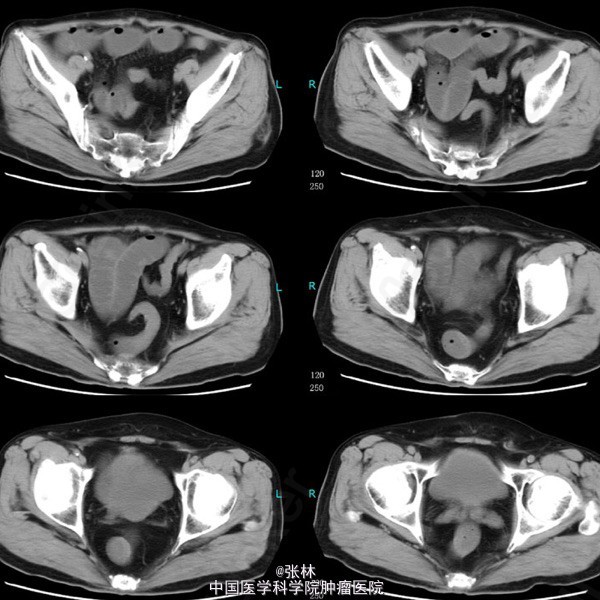

男性,72岁。 主诉:突发腹痛、腹胀伴呕吐1天。 现病史:患者1天前无诱因感全腹部疼痛,呈阵发性绞痛,无放射痛,疼痛开始不剧,伴有畏寒,呕吐胃内容物1次,量约30ml。遂到我院门诊就诊,考虑为急性胃肠炎,予抗炎、解痉护胃等支持治疗,症状未见好转,并进行性加重而入住我科。 专科检查:全腹稍胀,未见肠型及蠕动波,无上腹搏动。腹软,中下轻压痛,无反跳痛。全腹未及肿块,肠鸣音活跃,7次/分。 术中所见:探查见异物位于回肠距回盲部约50cm,大小约8*3*2cm,堵塞肠管,近端肠管充血水肿明显,肠管扩张最大处直径约8cm,未见浆膜层破裂损伤等,系膜无扭转,有少许渗液,探查全部小肠未及肿物腹腔内可见中等量黄色积液,稍浑浊,网膜及腹膜有少量脓苔。洗净腹腔内积液,于肿物边缘对肠系膜缘纵行切开约2cm,取出异物,为半个大小约8*3*2cm的冬菇。